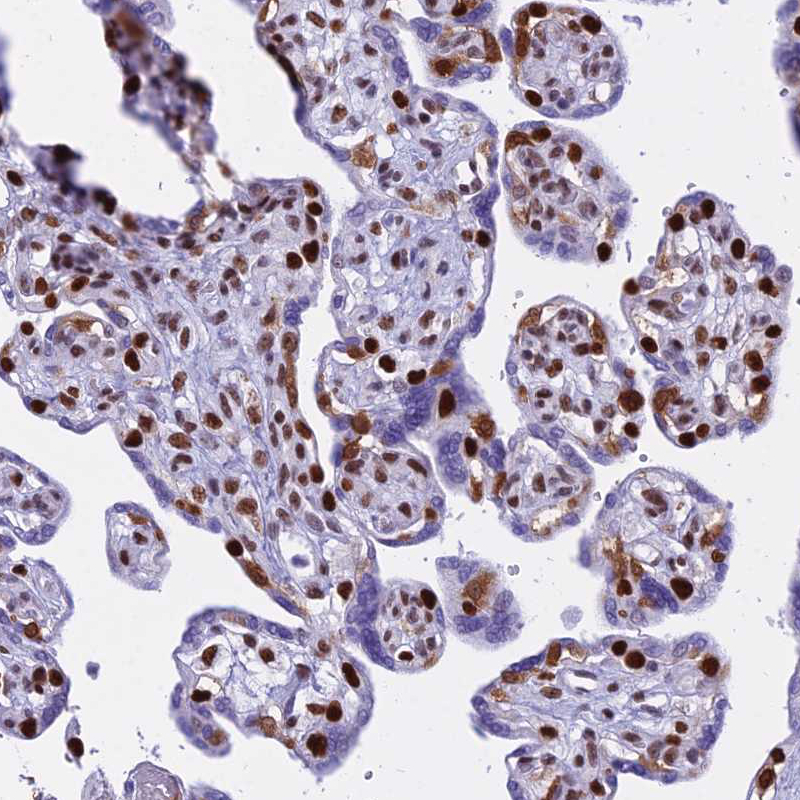

Immunohistochemical staining of human parathyroid gland shows strong nuclear positivity in glandular cells.